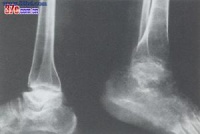

本病是在骨发育过程中发生的全身性、多发灶性、软骨坏死性疾病,造成的骨关节损害将持续终身,X

线征象归纳如下:

1.干骺端边缘模糊或凹凸不平,呈波浪状以至锯齿状。如病变继续发展,指骨端不整齐的边缘可呈碎裂现象。此时,关节无明显变形。

2.以骨骺与骨干开始融合为特征。骨骺自中央部分开始融合,渐扩展到边缘,骨骺本身亦有破坏、分节、不整等现象,也可能完全被吸收。干骺端可呈杯口状凹陷,骨髓嵌入其中而早期愈合,停止发育。

3.干骺完全融合,骨的纵向发育停止,病骨变短变粗。因为各干骺的融合迟早不同,以致各指骨可呈现长短不齐,骨端宽大变形,使关节粗大。

4.如干骺端愈合以后的青年发病,临床症状多见且严重。关节相对骨端都有损害,可影响整个关节,表现为大骨节畸形,可伴有短骨干。

5.大骨节病所见的系列征象都是软骨坏死后的修复和继发变化。只有经过修复组织特别是骨的改变塑型,病变才能发展到消退、稳定或发生畸形。

⑴、干骼型:以干骼端改变为主,包括临时钙化带变薄、模糊、中断、消失,干骼端出现凹陷、硬化等。干骺型发生于学龄前及学龄儿童,反映骺板软骨坏死后的继发变化,代表大骨节病较早的损害,临床症状多为阴性或非常轻微。干骺型的X线变化除很明显的硬化在非病区儿童中较少见外,其他征象均可在非病区儿童中出现。因而在同一地区没有发现Ⅰ度以上典型病例的情况下,不宜仅凭某几点干骺端X线改变就诊断为本病。前面谈过的日本发现的所谓大骨节病,就是由于没有充分注意到这一点。⑵、干骺骨骺型:除上述干骼端变化外,骨骺也有变化,如骨骺常呈锥状或其他变形,嵌入凹陷的干骺端等。此型多发生于学龄及青春期,反映骺板软骨的一部分发生全层坏死,其干骺侧和骺核侧同时有生长障碍和骨质变化,局部骺板早期穿通化骨。这是干骺型的进一步发展。

⑶、骨端型:以骨端改变为主,包括骨性关节面模糊不整、变薄、中断、凹陷变形、硬化、甚至碎裂等改变。多发生于学龄儿童至青春期以后年龄段,反映关节软骨深层坏死继发的骨质改变。骨端的变化发展较慢,合并其他关节损害多。骨端出现变化的诊断意义比干骺端的变化更重要,更具有特异性。

⑷、骨关节型:见于骺线闭合、骺板软骨消失之后,包括骨关节面的严重破坏、凹凸不平、增生硬化、骨刺形成、骨质碎裂、囊性变、骨端粗大畸形等改变。常累及多关节,X线所见类似退行性(增生性)关节病,是本病的晚期表现。